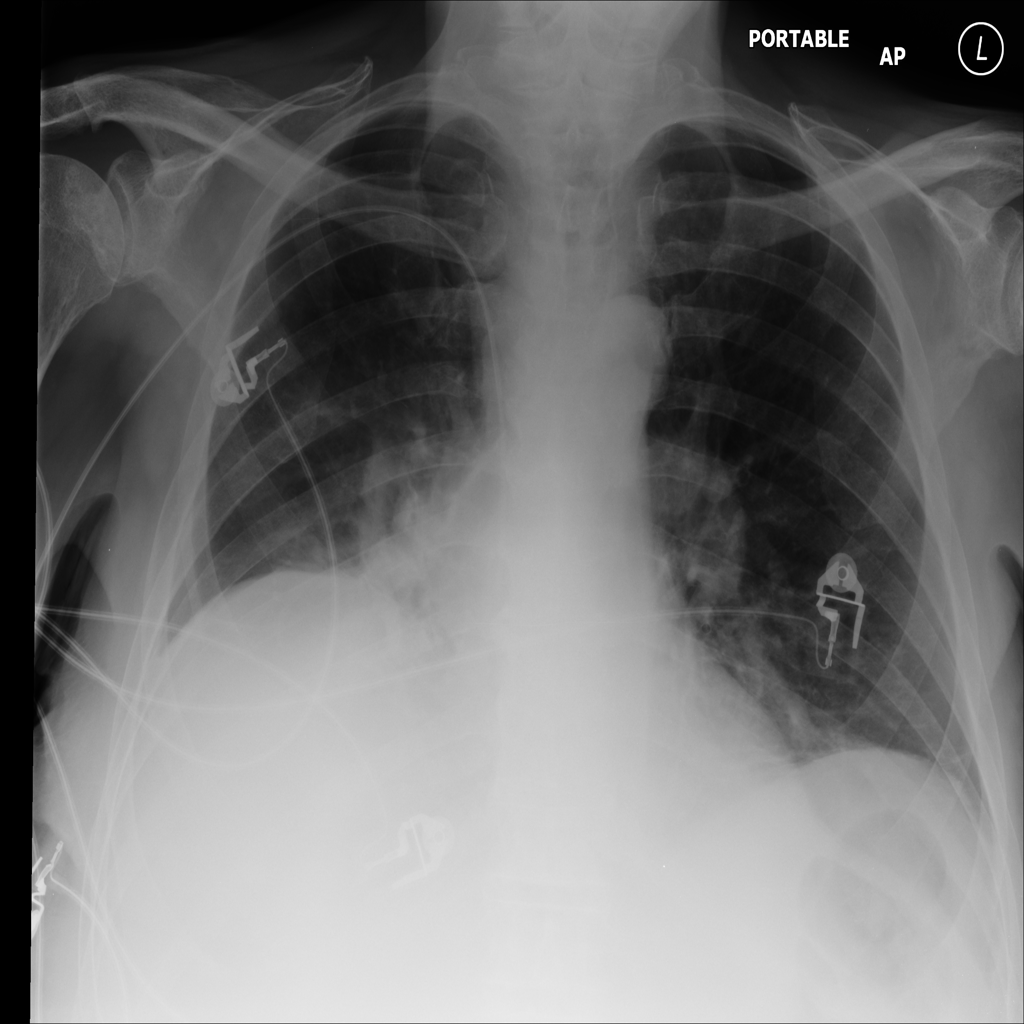

PAT-CD86 · IMG-023Atelectasis

PAT-CD86 · IMG-023

AP